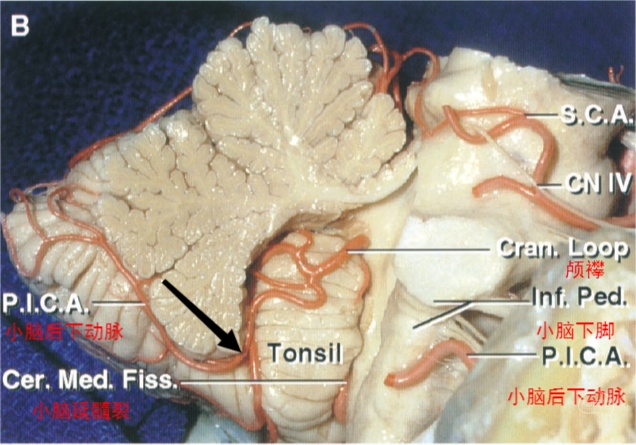

图4 小脑后下动脉内侧面观。图中黑箭所示为膜帆扁桃体段与皮层段的分界点,即小脑后下动脉离开小脑半球、小脑扁桃体及小脑蚓部之间裂隙处。皮层段分为内侧干和外侧干,内侧干供应小脑蚓部,外侧干供应小脑半球枕下面和小脑扁桃体。